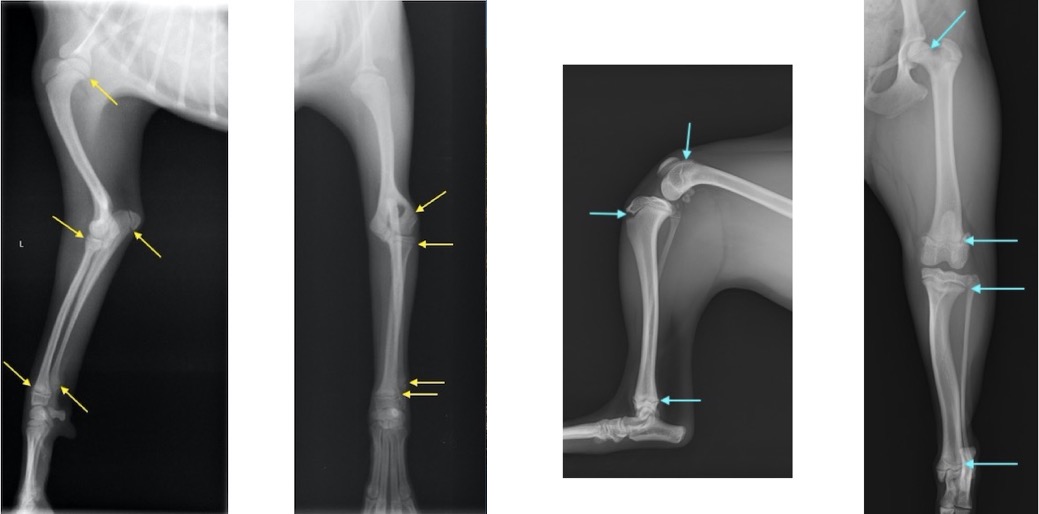

単純X線画像上の成長板(前肢と後肢) 矢印が成長板です。

成長板骨折の分類(Salter-Haris分類) 青いラインが成長板です。